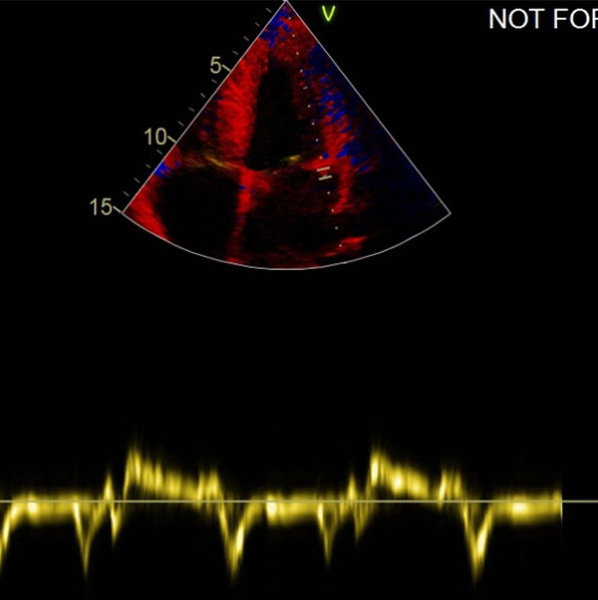

ETT :

- Hypertrophie ventriculaire gauche à prédominance septale (SIVd 12 mm, PPVG 12 mm) sans obstruction de repos, de fonction systolique conservée à 60 % en Simpson biplan. Cinétique homogène, SLG altéré à - 16 % en cocarde

- Profil mitral restrictif

Vidéo 3 : 4 cavités

Figure 8 : profil mitral type 3